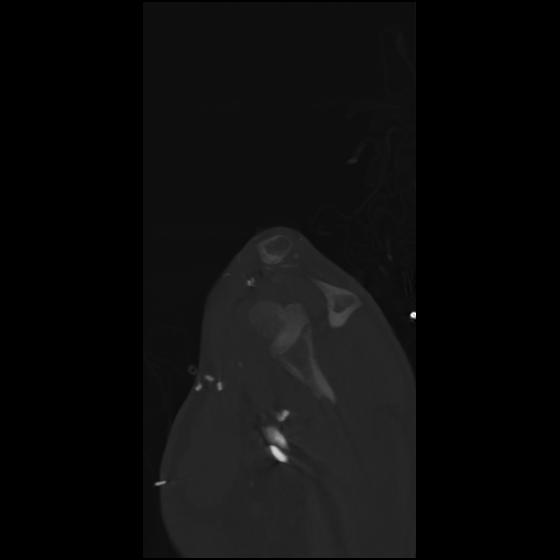

24 ANGIO,CE,Sag-MIP,5.000,ANGIO,Sag-MIP,